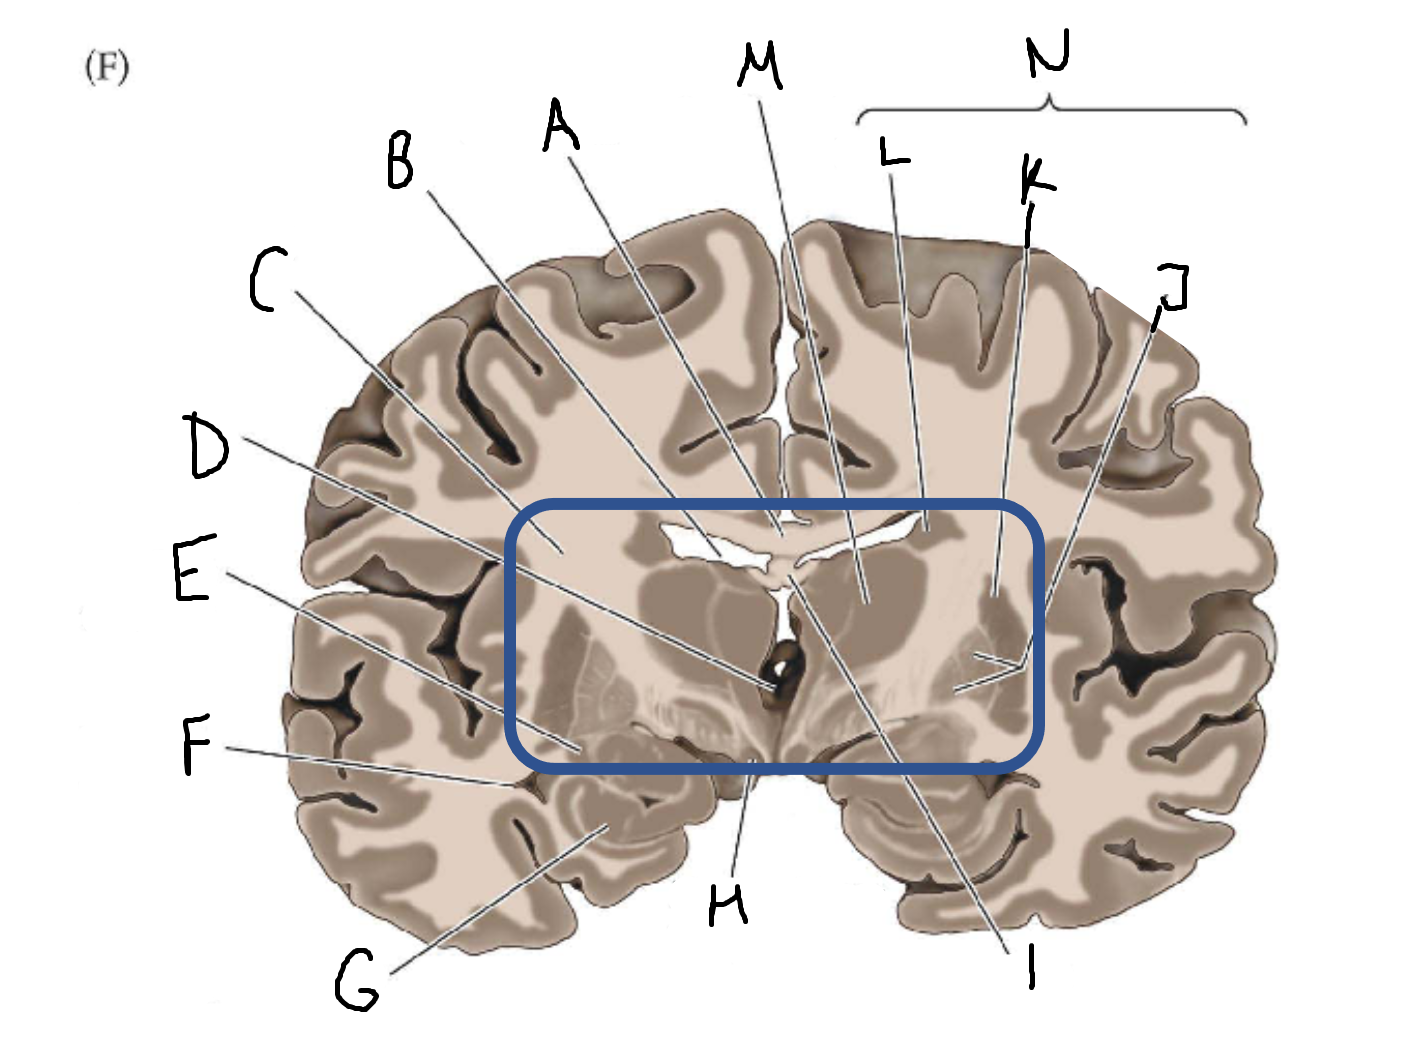

A

corpus callosum

B

lateral ventricle

C

internal capsule

D

third ventricle

E

tail of caudate nucleus

F

lateral ventricle

G

hippocampus

H

mammillary body

I

fornix

J

globus pallidus

K

putamen

L

caudate

M

thalamus

N

basal ganglia